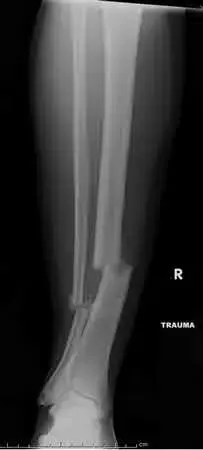

ORTHOPEDIC MCQS ONLINE OB 20 TRAUMA 2C week of indomethacin followed by 5 weeks of placebo, and (4) 6 weeks o…